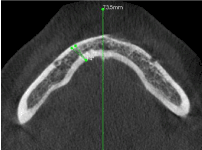

Figure 3. The distance between the lingual canal and the midline

Figure 10. The vertical angulation of the lingual canal at the lingual foramen

Figure 11. The vertical angulation of the lingual canal at the buccal end

Figure 12. The horizontal angulation of the lingual canal.